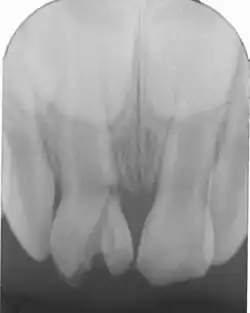

(De récentes études montrent qu'il y a de moins en moins de différence entre les deux sexes) En fonction des sites atteints :

- incisives supérieures touchées à plus de 90 % ;

exemple). À 3 ans nous sommes au stade de la maturation de l'émail avec la formation radiculaire donc toutes atteintes de la dent temporaire aura une projection sur le germe sous-jacent (tout ce qui se dirige vers le germe (infection, mouvement) présente un risque pour la dent permanente).